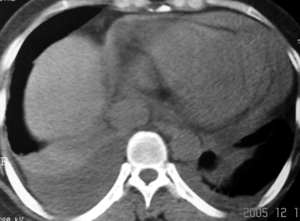

f43y昨日突发胸剧痛,今下午来医院并行ct平扫示:左下肺少许淡薄渗出病灶,双侧胸腔积液以右肺为甚,心包积液。

个人认为是心包积液,因为胸膜腔里的如果不包裹,易于流动,而此例病人心影周围的水是沿着心包腔的限制分布的,所以认为是心包积液

我认为,一般情况胸腔积液与心包积液并没有相关性,我们经常看到胸腔积液,但心包积液比胸腔积液要少。而这个患者心包积液较重,且发病较急,存在心包填塞的表现,右心房增大,说明回心血流受阻,肺淤血,可能会导致胸腔积液。该患者心包积液较重,建议进一步增强扫描。

心包积液基本可以肯定。两侧胸腔积液,心脏或肾脏病变或血浆蛋白过低都可引起胸腔积液。心包积液常拌有胸腔积液,可为单侧性或双侧性。上海一医大《x线诊断学》把其列为x线表现之一。

患者急性起病,影象学表现为大量心包积液和双侧胸腔积液,心包积液密度较高,应该考虑为积血,患者没有外伤史,自发性心包积血应该想到主动脉夹层动脉瘤心包内部分破裂的可能,主动脉根部明显增粗也支持该诊断。关于胸腔积液有两种可能的解释,一是由于夹层的压力很高,造成血性胸腔渗出;另外就是由于心包填塞造成腔静脉系统压力增高,引起胸腔的渗出改变。

心包大量积液,双侧行腔积液,升主动脉增宽,结合突然发病,不排除主动脉夹层破裂。